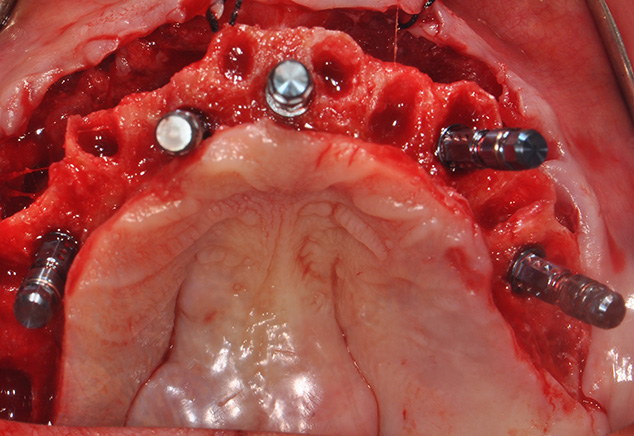

The implant sites were prepared using the manufacturer's protocol (except for bone tapping) for the Straumann BLT implant. The implants were placed using the surgical guide template with the following insertion torques measured: site: #4, #7, #8-9,#11,#13, #21,#23,#26. All torques were >35Ncm with #28 recording 20Ncm insertion torque values. All implants were 4.1mm in diameter and 14mm in length except #7, #8-9, and #11, which were 12mm in length (Fig 7). All 17 and 30 degree-angled implants were bone profiled prior to SRA abutment placement. This allowed the complete seating of the SRA abutment at the recommended 35Ncm torque. Using the available Straumann bone profilers with the appropriate Narrow Connection (NC) or Regular Connection (RC) inserts was a critical step for an abutment to fit correctly. The following SRA abutments (all were 2.5mm gingival heights) were then chosen: straight: #23, #26; 17 degrees: #4, #7, #8-9; and 30 degrees: #11, #13, #21, and #28. Tall protective healing caps were then placed (Fig 8), and the dentures were checked to evaluate that there was adequate space for the pink acrylic to allow for bite registration material thickness. All sockets and buccal gaps to the immediately placed implants were bone grafted. Prior to suturing, the tissue flaps were scalloped with 15c blades to reduce overlap of the flaps over the protective caps. This not only aided in post-operative healing, but also aided in the visualization of the abutments by the restorative dentist for the provisional insertion. The patient was sutured with resorbable 4-0 chromic gut and 5-0 Vicryl™ sutures (Ethicon: Johnson & Johnson) and was released to be seen immediately by Dr. Randel for the coordinated restorative visit. As discussed below, his responsibilities included: bite registration, impressions, and the dental lab conversion of the complete denture to a metal reinforced fixed transitional prosthesis (indirect provisionalization technique). Our team of restorative dentists have been treating full-arch immediately loaded cases on 5-8 implants (depending if restoration is a hybrid or C&B) since 1994. Our earlier experiences, for approximately the first two years (1994-1996), have us all presently using the indirect technique, which in our hands is easier for everyone involved (especially the patient). We handle these coordinated visits between offices, the dental lab, and our Straumann representative weeks prior so we are all on the same page with timing. These coordinated efforts could be compared to a symphony orchestra, where each musician knows their specific part and when and where they are expected to be. Many of our patients have described this fluidity as a seamless experience that they witness first hand and greatly appreciate.